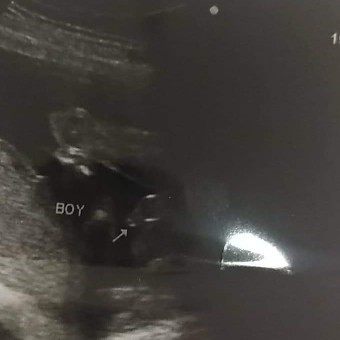

กองก้น โชว์ใข่ชัดมากกค้ะ 14 Week5Day😁💕

ทั้งพวงทั้งแท่งเลยคร้าบ 😊😁

คุณหมอบอกผู้ชาย100%คร้าบบบ😂😂